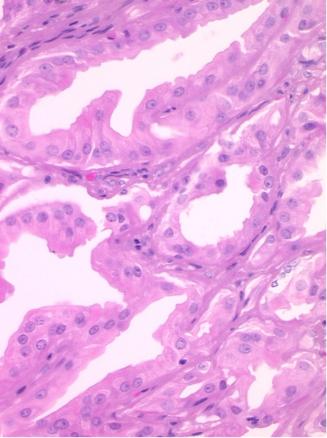

L’hidradénome papillifère est habituellement asymptomatique ; de rares douleurs et/ou saignements peuvent survenir en cas d’érosion de la surface. Le plus souvent, il prend l’aspect d’un nodule intradermique rond, unique, ferme, mobile, recouvert par une peau normale, de couleur rose, translucide, généralement de petite taille. Parfois, il a un aspect bleuté, exophytique et/ou ulcéré. Le diagnostic repose sur l’analyse histologique (fig. 3).